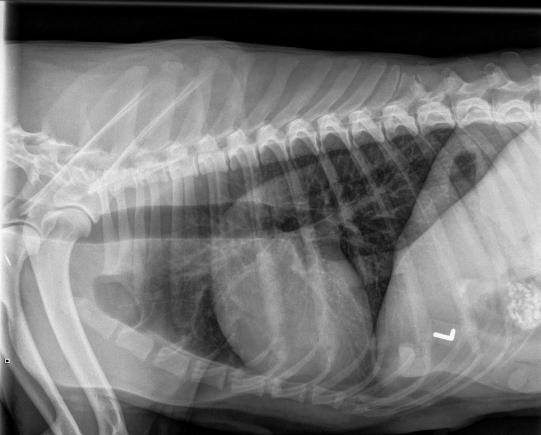

Nun geht es der Hündin glücklicherweise langsam besser, und 10 Tage später wird das Tier nochmals geröntgt: Die Lungenentzündung hat sich komplett zurückgebildet - allerdings lässt sich im Ultraschall aber auch keine Trächtigkeit feststellen.